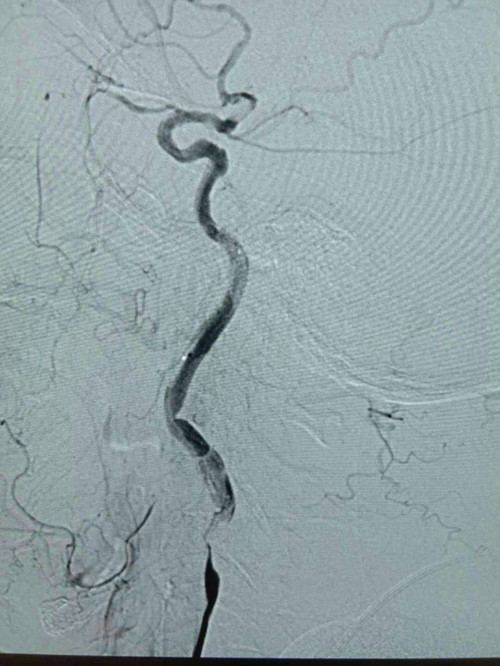

由于患者发病时间为3小时,神经内科医生立即通知介入中心小组成员,同时与家属交代病情,经家属同意,在导管室为患者进行股动脉穿刺。10分钟内穿刺成功,20分钟造影完成。造影结果显示右侧颈内动脉起始处闭塞,无良好代偿。医生给予微导管造影,判断闭塞段长度为15mm,缓慢注射阿替普酶5mg,血管内血栓逐渐溶解。因前段闭塞,仍未见有效血流,与家属再次沟通,决定开通闭塞的右侧颈内动脉。经过紧张、迅速的介入治疗,球囊扩张血管完成,闭塞段开通,残余狭窄85%,前向血流维持2a级,手术顺利完成。术后复查头CT未见出血,狭窄处择期支架成形治疗。术后患者神志清晰,言语较前流利,左侧肢体肌力由0级变为5级弱。